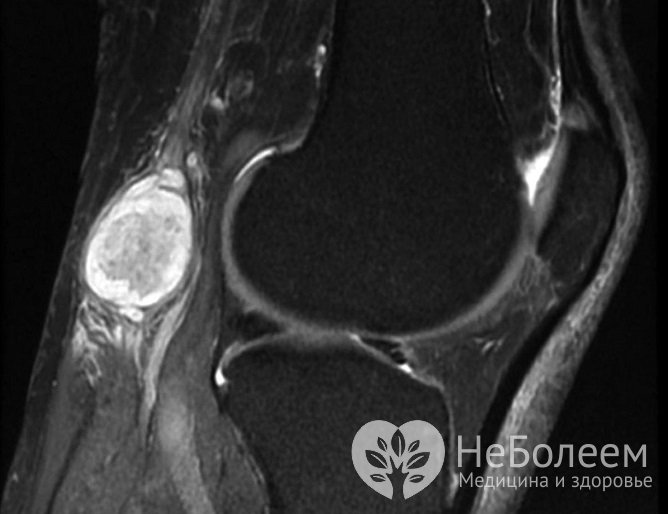

Киста Бейкера (Беккера, подколенной ямки) представляет собой скопление суставной жидкости в растянутой межсухожильной сумке, расположенной в подколенной области. Она формируется при различных заболеваниях коленного сустава. Является доброкачественным новообразованием, возникающим в любом возрасте, но чаще у пожилых людей. Во многих случаях протекает бессимптомно. Жалобы обычно появляются при ее значительных размерах и развитии осложнений. Возможны различные варианты лечения патологии: консервативное и оперативное.

При ультразвуковом исследовании кистозное образование на мониторе аппарата и фото обычно имеет вид образования вытянутой формы с четкими ровными контурами и плотной капсулой.